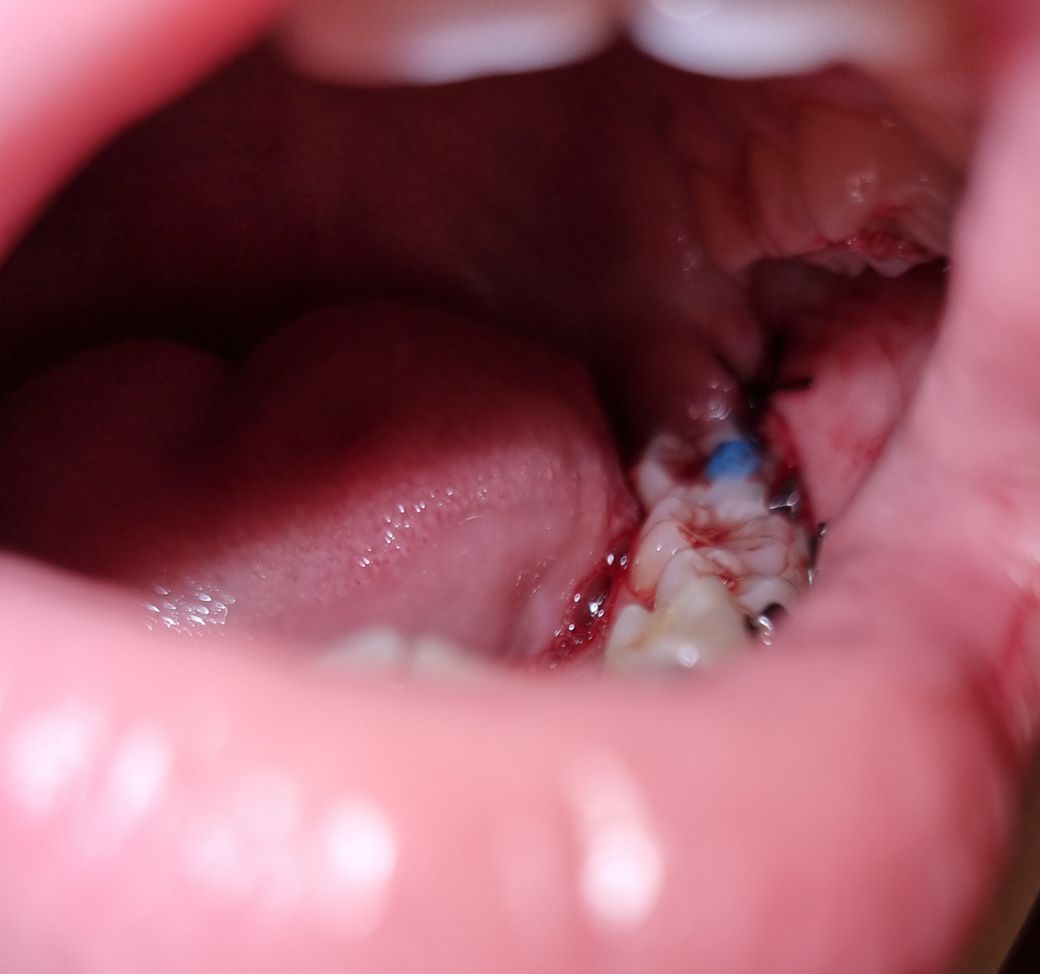

첫번째 사진은 발치 첫날 사진이고, 두번째 사진은 방금 찍은 사진입니다. 사진 상 잘 보이진 않지만 실밥이 끊어진 자리에 하얀색 거품? 흉터? 같은게 짜글짜글 자리잡고 있습니다

하얀색은 육아조직이라고 하는 조직이며 회복과정에서 나타나는 정상조직입니다.

사진상에서는 문제될 사항이 보이지 않으나, 만약에라도 실밥이 만약 느슨해졌거나 풀어졌다하더라도 대체로 2차 치유과정에 의해서 정상적으로 회복되므로 걱정하실 필요없으며,

만일 실밥이 심각하게 터졌더라도 다시 봉합해봤자 이미 상피화과정이 진행되었기때문에 소용이 없습니다.

즉, 걱정하실 필요없으며 기다리면 저절로 치유됩니다.

사진만 봐서는 실밥이 풀러진것인지 명확하진 않습니다. 잇몸이 부어서 저렇게 보이는것일수도 있습니다.

방문하지 않으셔도 됩니다. 실밥으로 해당 부위를 묶어 놓고 상피가 접합되기를 기대하는 것인데 이미 어느정도 상피가 회복되었습니다. 따라서 방문하지 않아도 되고 간혹 발치 이후에 실밥이 빠지시는 분들도 있지만 상관 없습니다. 또한 말씀하신 거품 및 흉터는 정상적인 회복과정의 일환입니다.